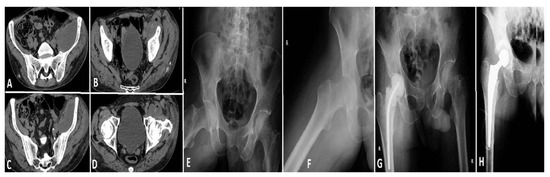

Case 1 (see Figure 6): A 67-year-old male with multiple comorbidities, including chronic renal failure, morbid obesity, diabetes mellitus, chronic heart failure, two coronary stents, and atrial fibrillation necessitating long-term anticoagulation therapy, presented with a septic infection of a hip prosthesis implanted approximately 10 years prior. The patient’s substantial comorbidities had a significant impact on both the surgical procedure and subsequent care. During his hospitalization, the patient displayed electrocardiogram (ECG) alterations suggestive of an ST-elevation myocardial infarction (STEMI) in the inferolateral region. Subsequent diagnostic assessments, including transesophageal echocardiography, identified the presence of vegetation on the aortic valve, indicative of endocarditis. The initial decision was to defer the planned cardiovascular surgery due to the patient’s rapidly deteriorating general condition and precarious health status. Instead, broad-spectrum antibiotics were provided. Following a two-week course of antibiotic treatment, the patient experienced a spontaneous splenic rupture, necessitating an emergency splenectomy; the patient’s condition continued to deteriorate. A subsequent transesophageal ultrasound revealed further expansion of the valvular vegetations, necessitating immediate valvuloplasty. The procedure was completed successfully, and the patient was initiated on a robust anticoagulant regimen postoperatively. A computed tomography (CT) scan of the hip revealed the presence of periprosthetic collections, thereby confirming the persistence of the local infection. A revision arthroplasty was performed, during which a cemented prosthesis was inserted to replace the contaminated hardware. Despite these interventions, the patient’s general health continued to deteriorate due to the complexity of his medical condition and the persistence of the infection. Despite comprehensive antibiotic therapy, surgical procedures, and intensive care support, the patient experienced multi-organ failure and ultimately succumbed to their illness after approximately six weeks of treatment.

Figure 6. Images (A,B): The presence of a notable fluid collection in the hip region suggests the possibility of a periprosthetic infection. The presence of this accumulation was a crucial factor in the diagnosis of the infection. Image (C): A splenic lesion is observed, necessitating a splenectomy due to spontaneous rupture resulting from infectious complications. Image (D): The presence of valve vegetations on the aortic valve necessitates the performance of a valvuloplasty. The vegetations were identified through the utilization of transesophageal echocardiography, a diagnostic technique employed to assess the patient’s condition. Image (E) depicts the postoperative status of the hip, which has been fitted with a negative pressure drainage device to facilitate wound healing and reduce the accumulation of contaminated fluid.